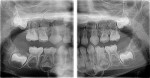

Several optional features are available on digital panoramic units from various manufacturers. Features include: 1) variable arch shapes; 2) curved linear projections of the temporomandibular joints, maxillary sinuses, and cross sections of the jaws; 3) automatic exposure control; and 4) panoramic bitewings (Figure 2).8-12